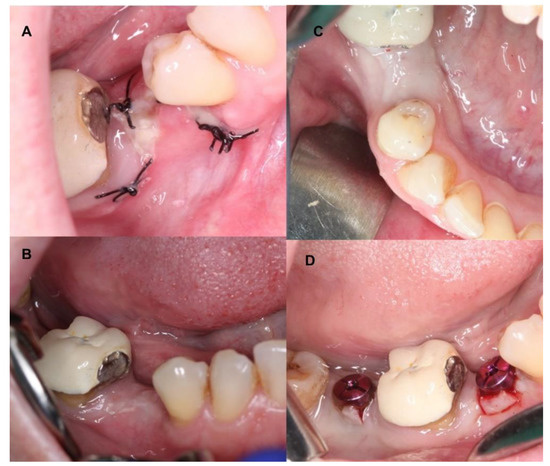

4.1. Patient No. 1

4.2. Patient No. 2

4.3. Patient No. 3

4.4. Patient No.4

4.5. Patient No.5

4.6. Patient No.6

| 1 F 63 | NO [Tobacco: 2 cig/day] Horizontal Guided Bone Regeneration | Yes [No] | G | No | G | No | No |

| 2 M 52 | NO [-] Alveolar ridge preservation | No [Yes] | G | No | M | Graft loss and self-limited alveolitis | No |

| 3 M 61 | NO [-] Alveolar ridge preservation | Yes [No] | G | No | G | No | No osseointegration of the implant, replacement in 3 months, without problems and with good stability |

| 4 F 46 | NO [-] Alveolar ridge preservation | No [Yes] | G | No | M | Graft loss and self-limited alveolitis | No |

| 5 M 64 | NO [-] Sinus lift with lateral window | Yes [No] | G | No | G | No | No |

| 6 M 46 | NO [-] Sinus lift with lateral window | Yes [No] | G | No | G | No | No |